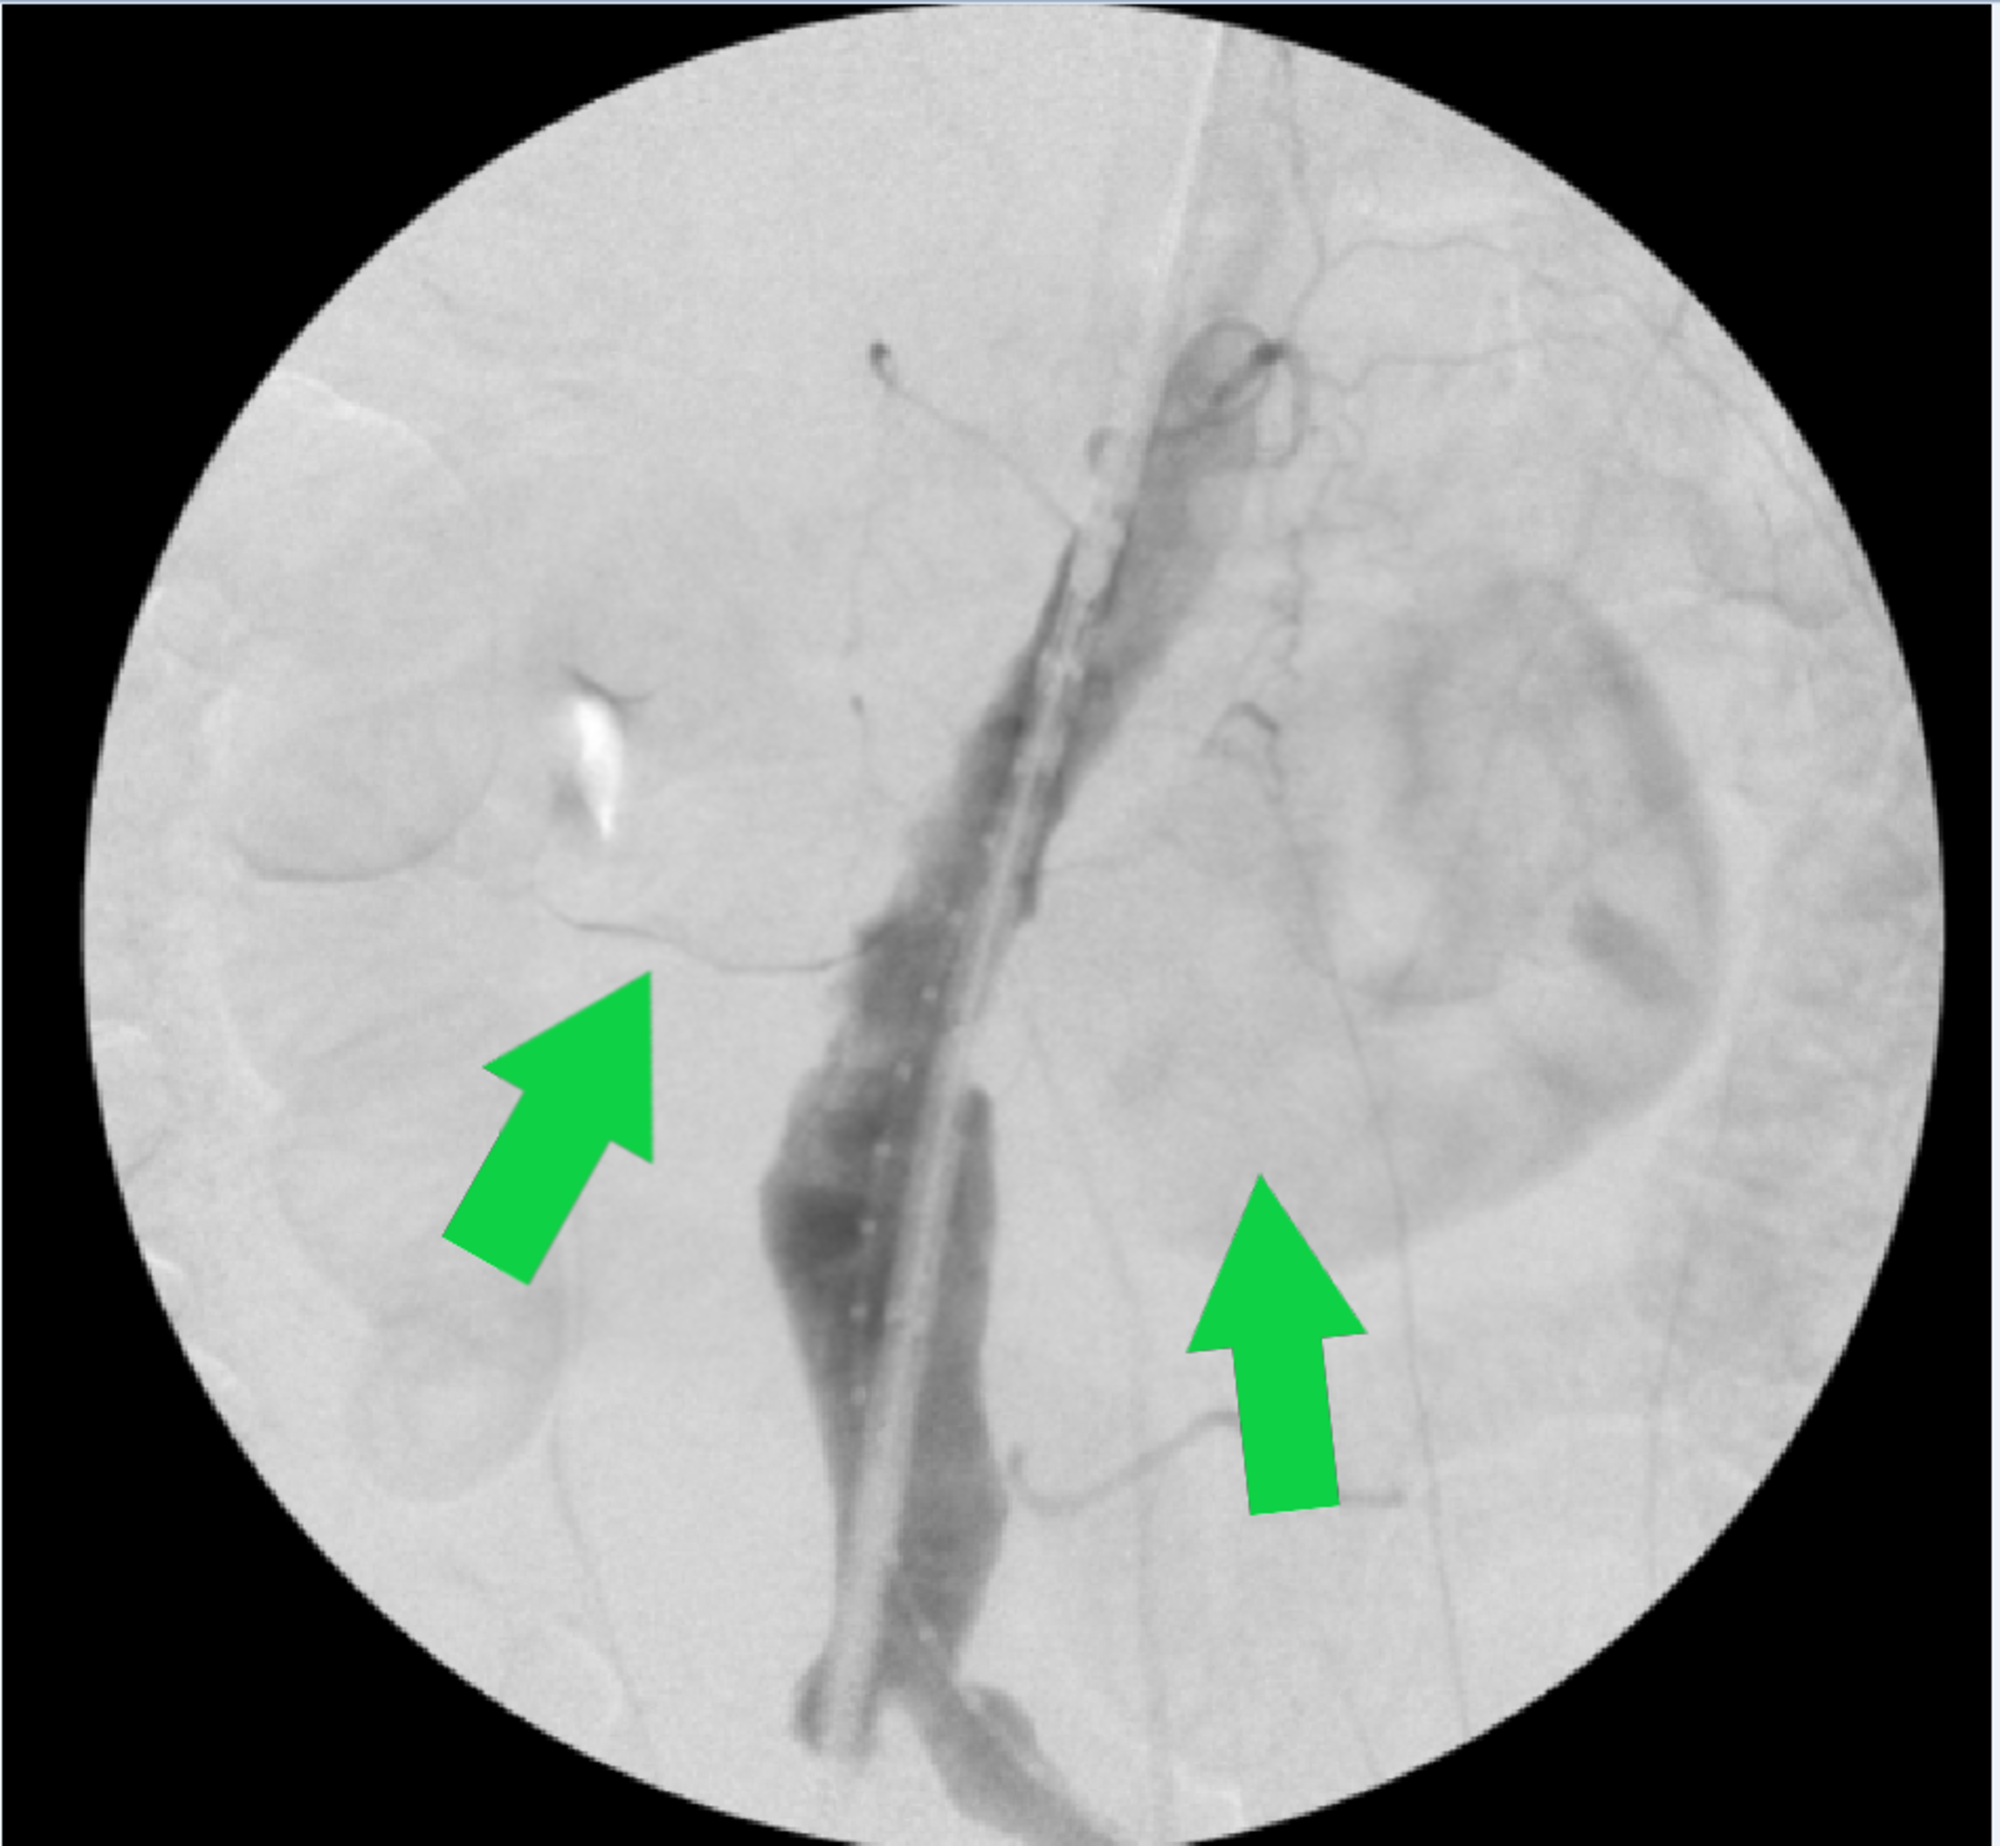

(PDF) Exclusion of an Infrarenal AAA with Coincident Horseshoe Kidney Horseshoe Kidney Aaa Coexistence of horseshoe kidney and abdominal aortic aneurysm (aaa) is a rare entity that presents a technical challenge to vascular. Ten patients with abdominal aortic aneurysms (aaas) and horseshoe kidney were treated with endovascular aneurysm repair. A horseshoe kidney (hsk) is a rare anatomic anomaly, with a prevalence of 0.12 percent, that poses significant challenges in the repair of. Horseshoe. Horseshoe Kidney Aaa.

EVAR Approach for Abdominal Aortic Aneurysm with Horseshoe Kidney A Horseshoe Kidney Aaa Horseshoe kidney (hsk) is a rare congenital fusion defect and is uncommonly associated with abdominal aortic aneurysm. Horseshoe kidney (hsk), referring to the abnormal fusion of the lower renal poles, represents one of the most common renal. Ten patients with abdominal aortic aneurysms (aaas) and horseshoe kidney were treated with endovascular aneurysm repair. A systematic review of all patients that. Horseshoe Kidney Aaa.

Horseshoe kidney and AAA, with the inferior vena cava (marked by blue Horseshoe Kidney Aaa Coexistence of horseshoe kidney and abdominal aortic aneurysm (aaa) is a rare entity that presents a technical challenge to vascular. Horseshoe kidney (hsk) is a rare congenital fusion defect and is uncommonly associated with abdominal aortic aneurysm (aaa). A systematic review of all patients that have been reported in the literature with abdominal aortic aneurysm (aaa) concomitant. Horseshoe kidney (hsk). Horseshoe Kidney Aaa.